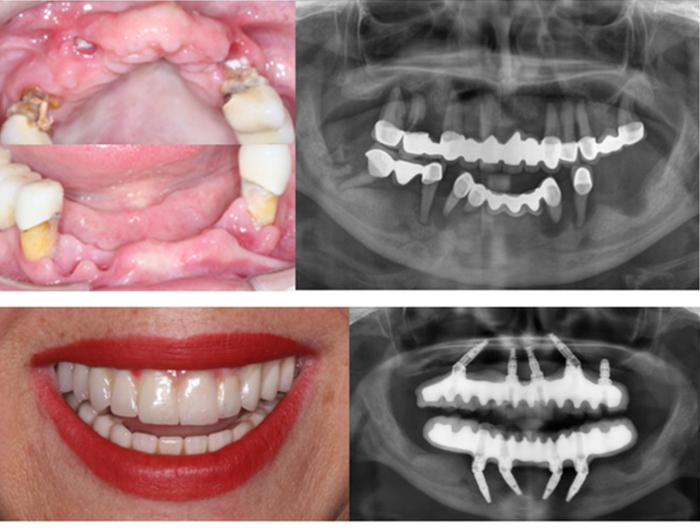

那么,改善牙齿咬合状态能否降低血糖水平呢?为解答这个问题,研究人员在想要重建牙齿咬合的志愿者身上中进行了相应的种植体支持固定修复手术以改善咬合状态及牙齿排列情况。他们发现手术后A1c水平逐渐下降,1年半后血糖水平显著降低。

图片:种植体支持固定修复手术前(上图)和手术后(下图)患者牙齿排列及咬合情况

图片来源:参考文献【1】